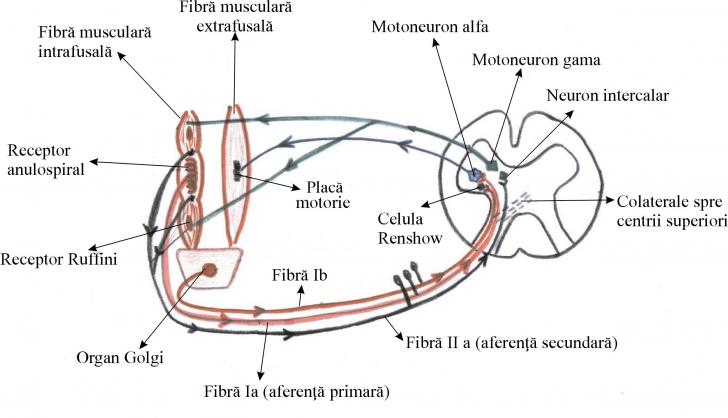

BAZELE TEORETICE ALE KINETOLOGIEI MEDICALE - FIZIOLOGIE NEUROMUSCULARA

BAZELE TEORETICE ALE KINETOLOGIEI MEDICALE - FIZIOLOGIE NEUROMUSCULARA Una din functiile cele mai importante ale SNC este controluCiteste tot ... 1590 cuvinte

Dimensiune medie

+ cu poze |